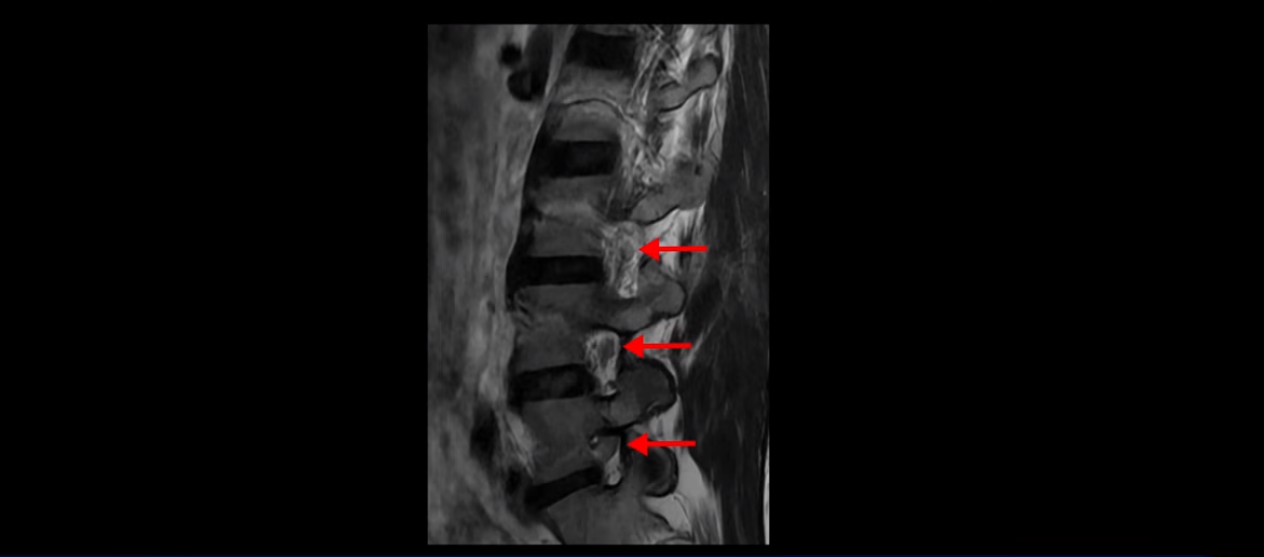

우선 이분 허리 MRI를 보면 5번 1번에 퇴행성 디스크가 있지만 방사통을 일으킬 만큼 신경을 누르고 있어 보이지 않습니다.

오른쪽으로 디스크가 약간 찢어져 보이는데, 작년에 찍은 MRI에서도 보이는 것이라 오래 전에 찢어진 후 아문 흔적으로 보입니다.

중요한 것은 오른쪽 다리에 심한 방사통이 있다든가 재채기를 못 한다거나 허리를 구부리거나 몸을 살짝 비틀 때 날카로운 통증이 없습니다. 즉, 섬유륜이 최근에 찢어진 게 아닌 겁니다.

4번 5번과 3번 4번 마디도 디스크가 중앙으로 살짝 밀려나와있지만 최근에 섬유륜이 찢어진 것도 아니고, 신경 다발을 누를 정도로 심하게 밀려나와 있는 것도 전혀 아닙니다.

양쪽 신경 가지가 빠져나가는 추간공도 충분히 넓어서 신경학적 방사통을 일으킬 여지가 없습니다.

그럼 이 환자분의 양쪽 다리 저림과 발 저림 그리고 앉기만 하면 5분 내로 심한 허리 통증, 엉덩이 통증이 발생하는 원인은 뭘까요? 저희가 이런 디스크 내장증 얘기를 들으신 환자분들 치료 후기에서 수없이 설명하지만, 이런 증상이 디스크가 원인이 아닙니다. 이분도 여러 병원에서 증상과 MRI가 일치하지 않는다고 들으셨는데요.